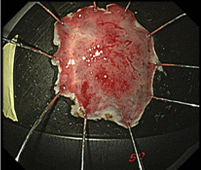

治療困難例でも卓越した技術で切除

表在型食道がん 亜全周症例

早期大腸がん 内視鏡治療後再発例